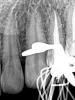

Magdalena Опубликовано 2 ноября, 2011 Поделиться Опубликовано 2 ноября, 2011 Вообще никакой гель не использую. Только хлорка. ЭДТА только в жидком видеВот кстати, благодаря форуму стала жидкой ЭДТА мыть - стала латеральки пропечатывать. 3 года их ждала))) Ссылка на комментарий

ger_berra Опубликовано 2 ноября, 2011 Поделиться Опубликовано 2 ноября, 2011 (изменено) Вот кстати, благодаря форуму стала жидкой ЭДТА мыть - стала латеральки пропечатывать. 3 года их ждала)))На первом снимке показалось,что немного недопаковано в апексе.Или констрикция такая? А второй очень красивый! Изменено 2 ноября, 2011 пользователем ger_berra Ссылка на комментарий

Magdalena Опубликовано 2 ноября, 2011 Поделиться Опубликовано 2 ноября, 2011 На первом снимке показалось,что немного недопаковано в апексе.Или констрикция такая? А второй очень красивый! В 2.2 апикальный упор на 1мм от верхушки. Ссылка на комментарий